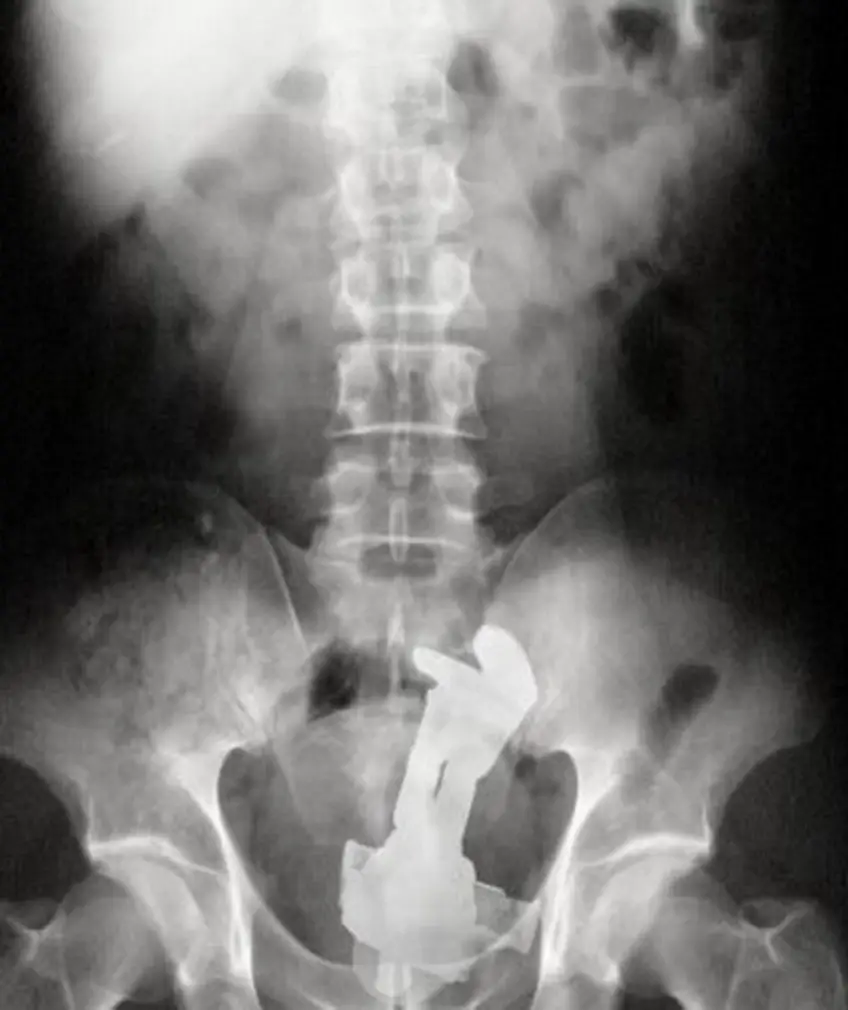

MEDICINA ONLINE OGGETTI CORPO ESTRENEO ANO BAMBINO ESOFAGO STOMACO BATTERIE SEX TOYS OGGETTI SESSO GIOCATTOLI TOSSICI BOTTIGLIA PENNA PENNARELLO COLON RETTO RISCHI COSA FARE COLONSCOPIA

Published 18/04/2018 at 1016 × 1211 in Corpi estranei nel tratto digerente: rischi e cosa fare in bambini e adulti

MEDICINA ONLINE OGGETTI CORPO ESTRENEO ANO BAMBINO ESOFAGO STOMACO BATTERIE SEX TOYS OGGETTI SESSO GIOCATTOLI TOSSICI BOTTIGLIA PENNA PENNARELLO COLON RETTO RISCHI COSA FARE COLONSCOPIA INTESTINO DIGERENTE RX RADIOGRAFIA